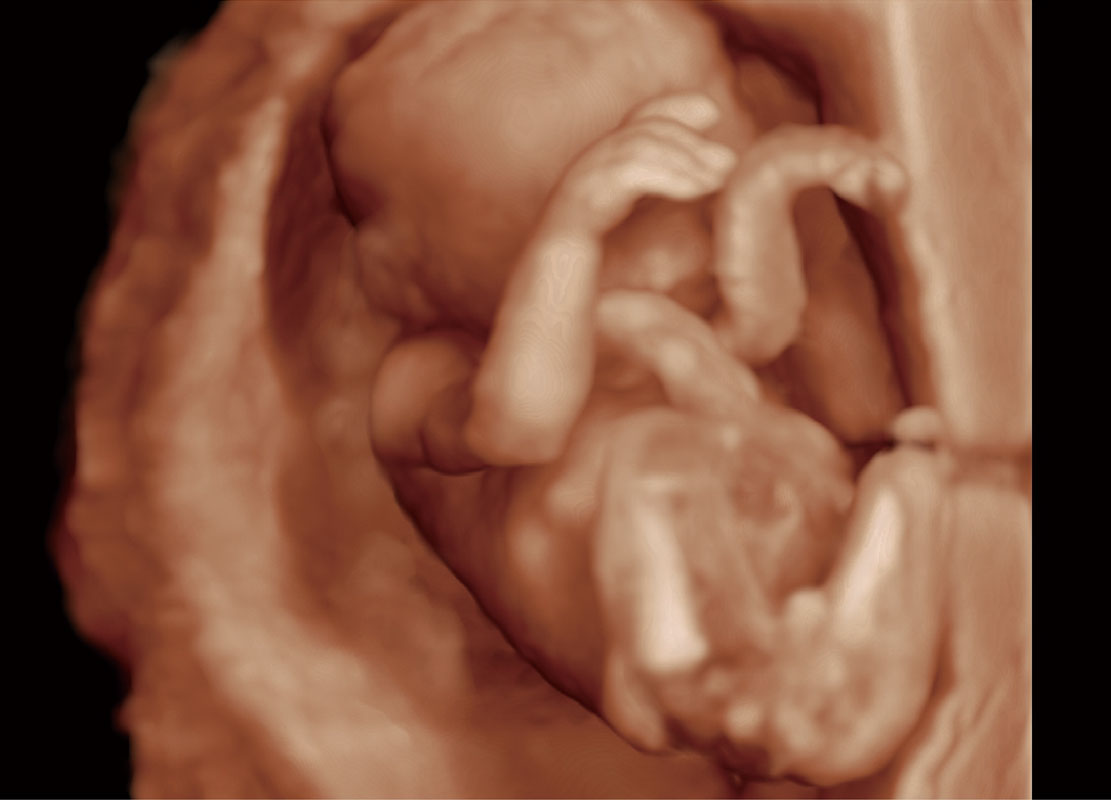

早孕筛查

P60在胎儿早孕期超声筛查中为您带来优异的图像质量。

• 早孕-胎心

• 高分辨率容积成像-早孕胎儿

• 胎儿体循环

• 光影成像-孕囊